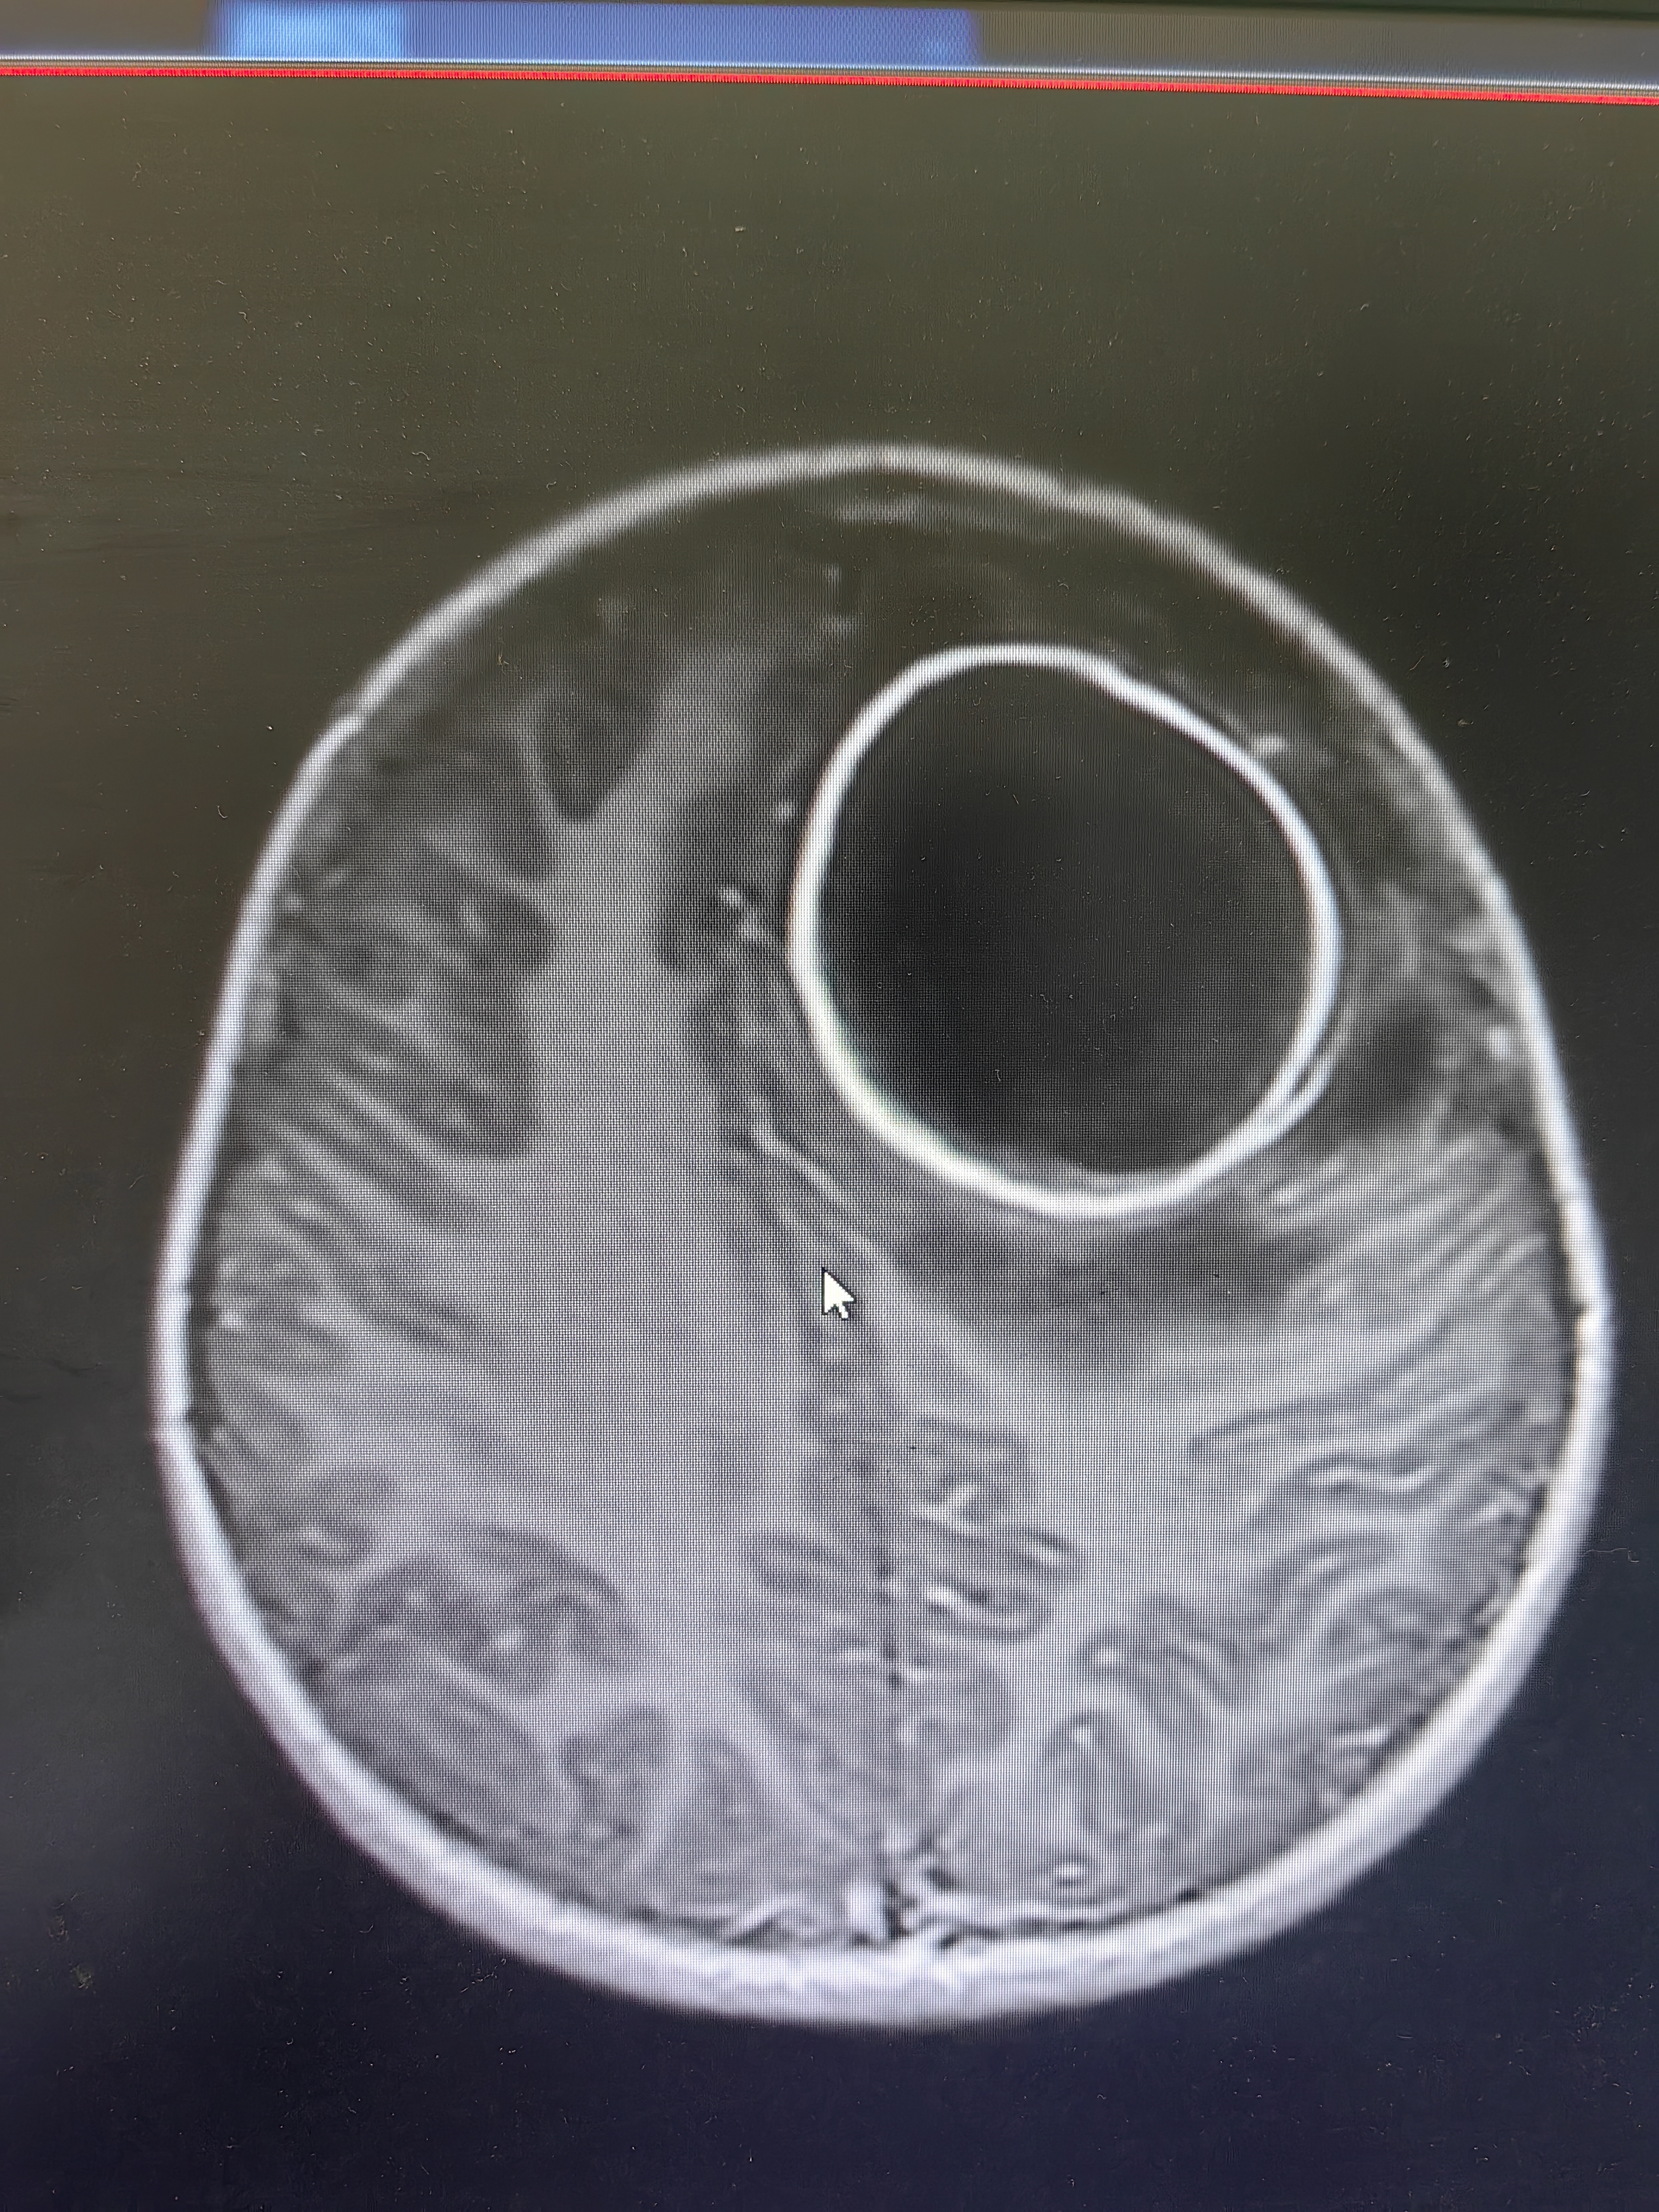

脑脓肿穿刺引流术引流

穿刺

脑脓肿